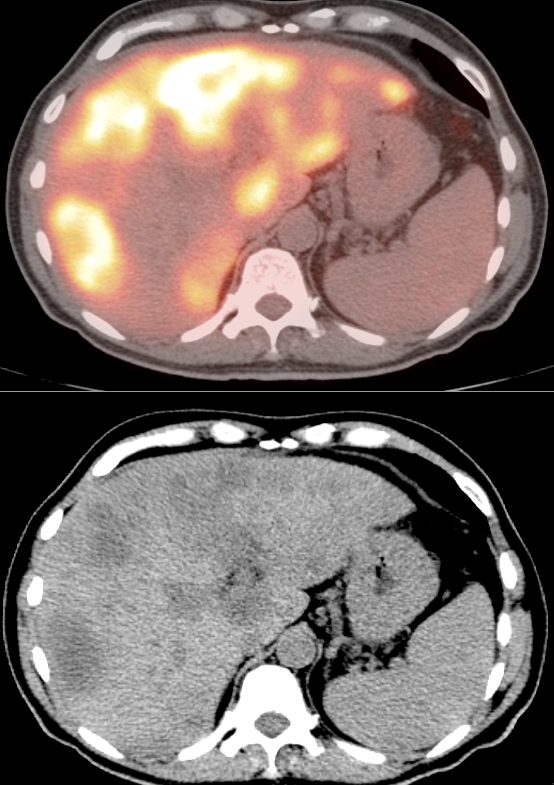

Metastases:

The most common sites of metastatic disease include the lymph nodes (regional & distant), liver, lung, peritoneal cavity, bones, brain and adrenal glands.

• Mucinous adenocarcinomas and necrotic tumors can have low avidity for FDG.